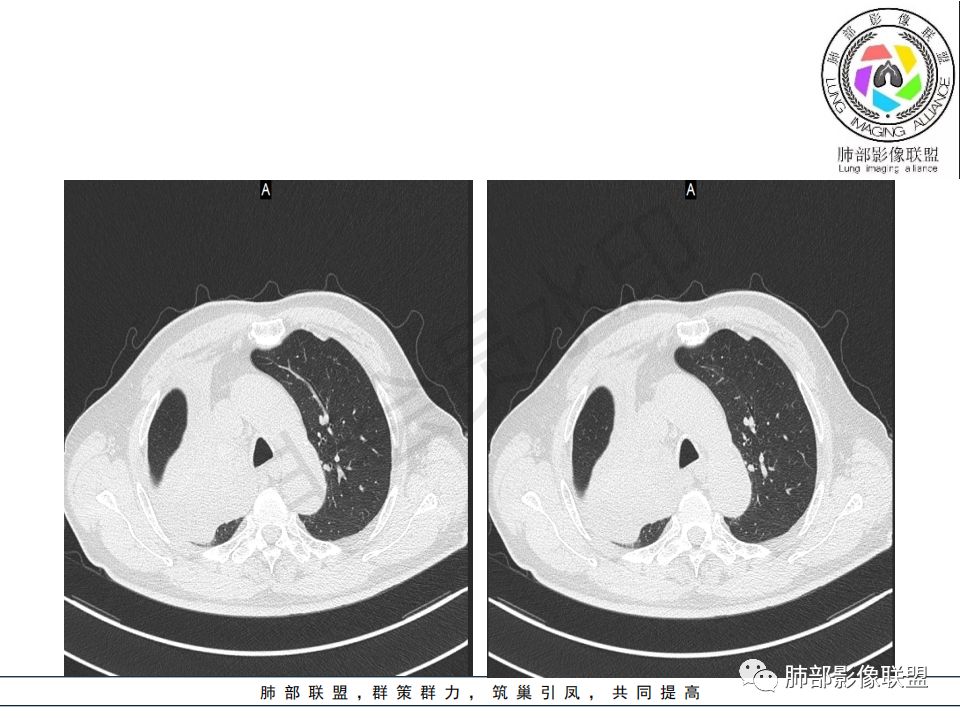

晨读:患者老年男性,以咳嗽一月就诊,少量白痰,胸CT:纵隔右移,右肺体积缩小,气管下段管壁可见结节样改变,气管软骨变形,气管下段及右主支气管可见新生物向管壁浸润,并向管腔外生长,右上肺肺不张,但不张边缘可见病灶呈膨胀性生长,可见分叶,增强后强化明显。考虑:肺部恶性病变(鳞癌?)

右肺上叶肿块,边缘光滑,略膨隆,近段支气管堵塞,平扫密度均匀,增强后不均匀强化,其内可见不规则血管和坏死,纵隔淋巴结肿大,老年男性,无感染性病史,综合考虑恶性肿瘤(鳞癌,腺癌),鉴别:OP(一般下叶多见)

如果鳞癌这么大,破坏力应该很大吧,肋骨会不会受累?当然这例气管壁受累,截断,远端阻塞性肺不张,还是符合中央型肺癌,特别是鳞癌的

老年男性,右肺气管内软组织影,支气管变窄截断,右肺上叶阻塞性肺不张,内见细点状钙化,周围看见小结节,增强不均匀强化,考虑:原发肺恶性鳞癌。胃癌病史,转移不出外。鉴别神经内分泌癌,类癌。

从强化情况和冠状位看主要还是从外向内的一个肿块,有不张,但不张范围不大,近端支气管堵塞,考虑腺癌或类癌(原发或转移都可能),鉴别鳞癌。